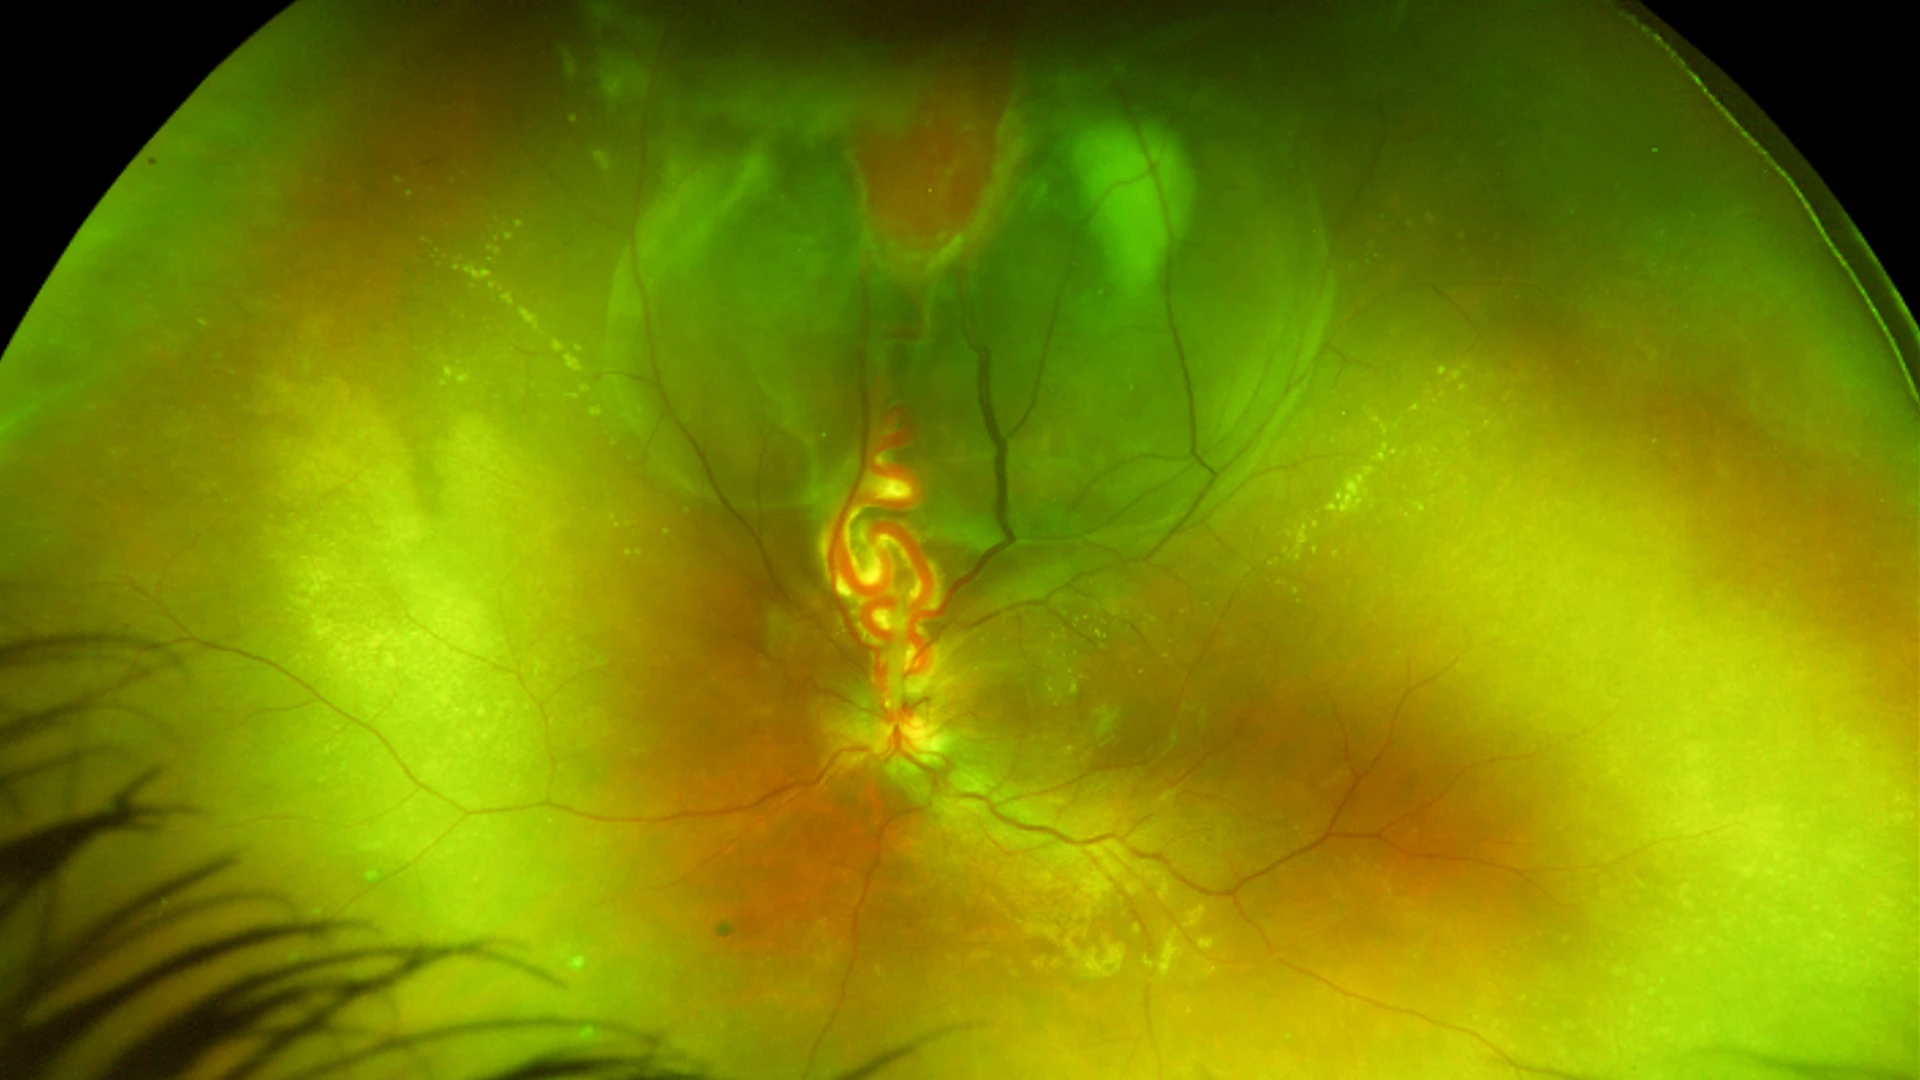

Over the prior year, two attempts to treat the tumor through conventional laser surgery were undertaken by Ekaterina Semenova, MD, an ocular oncologist and Director of Pediatric Ocular Oncology at NYEE and The Mount Sinai Hospital. The retinal damage from this rare tumor, known as a retinal capillary hemangioblastoma, was found to be already considerable when Dr. Semenova first saw the patient. Though noncancerous, it had led to the development of a large retinal detachment that had been slowly growing over the years and had gone unnoticed until it resulted in severe loss of vision in the affected eye.

Fundus image of the tumor with a retinal detachment and the dilated feeder blood vessels